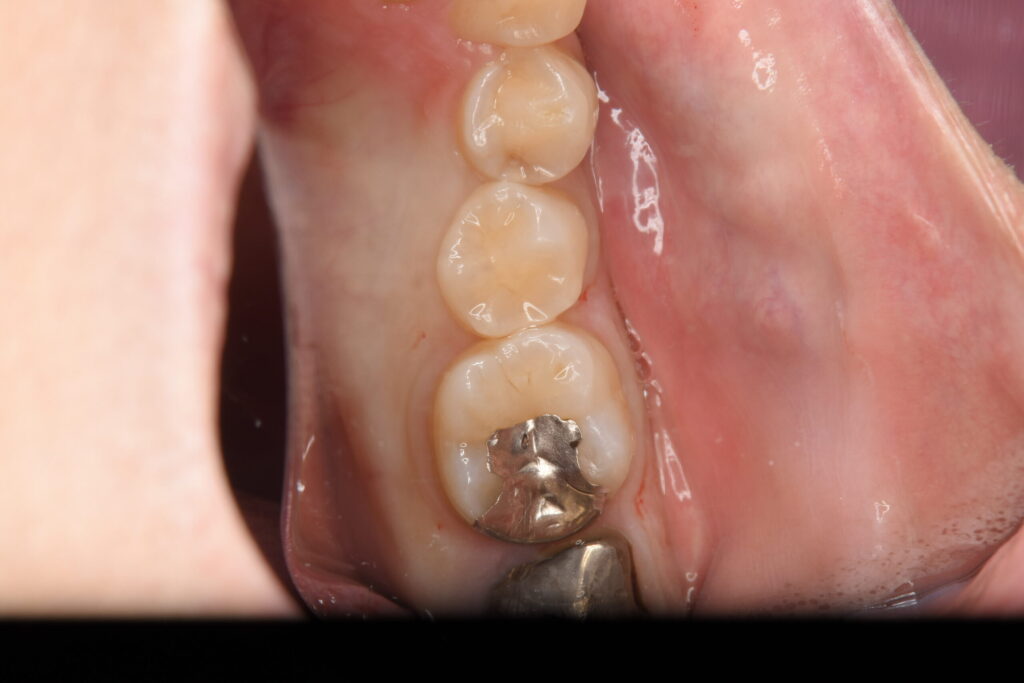

レントゲン検査にて、銀歯の下に虫歯を認め、その周囲の虫歯と共にダイレクトボンディングにて治療を行なった。

| 虫歯のダイレクトボンディング治療(40代女性) |

| 銀歯が入っている歯が痛い |

| 銀歯の下の虫歯とその周囲の歯の虫歯をダイレクトボンディングで治療を行なった。 |